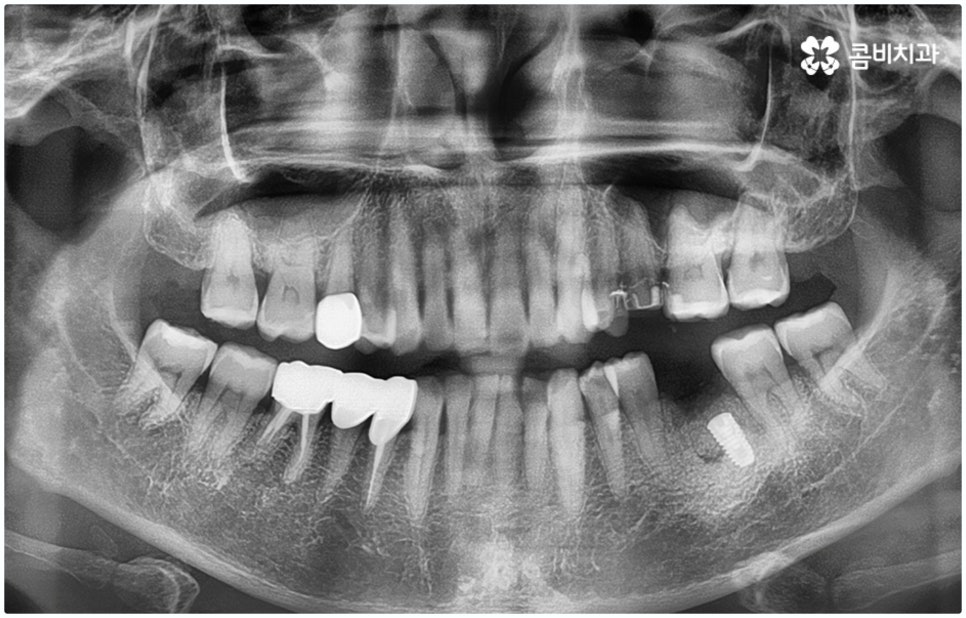

통상적으로 임플란트 시술 과정이 3~6개월 정도 소요되는데 반해 원데이임플란트 란 말 그대로 발치 후 식립 및 임시보철물까지 당일에 장착하는 방법이기 때문에 많은 분들이 선호하시고 있는데요. 하지만 누구나 원데이임플란트 치료가 가능한 것은 아니므로 검진부터 받아보셔야 할 거예요

임플란트 시술은 사람의 잇몸뼈와 잘 붙고 인체에 무해한 인공치근(픽스처)을 식립한 후 중간 연결 부분인 지대주와 치아 머리 부분인 크라운을 차례대로 연결하여 기능상 심미상으로 자연 치아를 대체해 주는 인공 치아 식립 방법으로 보통 픽스처를 심을 때 잇몸뼈와 제대로 유착되는 시간이 필요하기 때문에 중간에 일정 시간 회복기를 두고 진행하게 되어 있어요.

이때 환자분들의 상황에 따라 잇몸뼈가 충분하지 않다면 먼저 뼈이식을 통해 이를 단단하게 보충해 주기도 하고, 치주 질환의 치료가 필요하거나 상악동과의 거리가 너무 짧아 거상술이 필요한 경우 이를 선행하기도 하기 때문에 전체 기간은 개개인에 따라 달라질 수 있으며 특히 구강 상태나 연령에 따라 충분한 회복 및 적응 시간을 두지 않으면 식립 성공률이나 장기적인 지속성에 좋지 않은 영향을 줄 수 있으니 주의할 필요가 있습니다.

그렇기 때문에 무조건 보다 빠르고 간편하다고 해서 원데이임플란트 방법을 고집하기 보다는 개인 상태에 따라 필요한 과정을 세심하게 맞춤 진행할 수 있도록 경험이 풍부하고 노하우가 뛰어난 의료진에게 치료 받는 것이 중요한 거예요. 즉 3D CT 등 정밀 검진 장비를 이용하여 환자분들의 치아 및 잇몸 상태, 치아 배열과 교합상태, 주변 치아와의 관계 및 조화까지 꼼꼼하게 파악할 뿐 아니라 턱뼈, 혈관, 신경 등 구강 전체를 함께 분석한 후 체계적인 시술 계획을 세워 각자에 맞는 방법으로 무리하지 않게 수술을 진행할 수 있는 숙련된 의료진과 함께 하는 것이 무엇보다 중요하다고 할 수 있습니다.